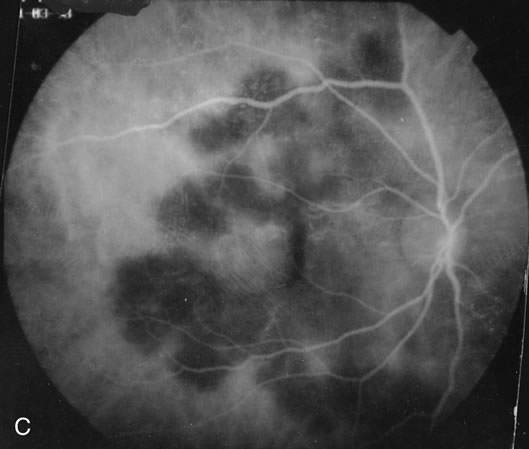

Some patients present with subretinal bands that extend between chorioretinal scars. In addition there may be initial active yellow choroidal lesions that subsequently become atrophic. Vitreous cells are usually present although they may be few and difficult to detect. Visual acuity loss in these cases may be due to active choroidal neovascularization, subretinal bands under the fovea, or from cystoid macular edema. The vast majority of affected patients are women with a mean age of 27 years and both eyes are usually involved. The affected individuals tend to be myopic.49 The age range is from 6 years to 76 years and there is no racial predilection.40 Whether it is a separate disease or a more severe form of multifocal choroiditis is controversial (Figs. 10 and 11). Aggressive therapy is warranted because it has a poorer prognosis than most cases of multifocal choroiditis. This syndrome has been called either diffuse subretinal fibrosis or progressive subretinal fibrosis syndrome.

Fig. 11. A. Subretinal fibrosis in a case of multifocal choroiditis. B. Fellow eye showing classic coalescent hyperpigmented chorioretinal scars of multifocal choroiditis. These scars also can be seen in presumed histoplasmosis syndrome, but the subretinal fibrosis is extremely rare in presumed ocular histoplasmosis syndrome (POHS).